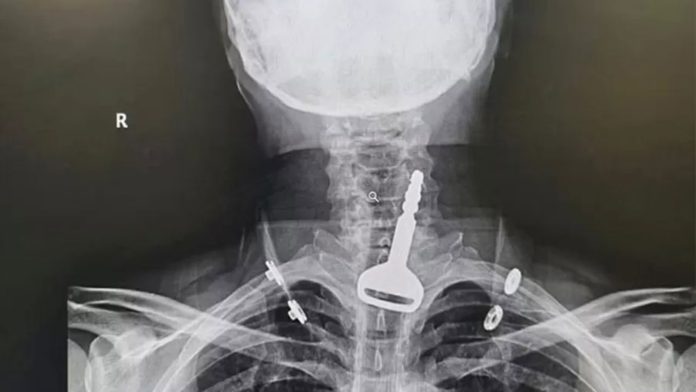

Um homem de 49 anos quase morreu asfixiado após engolir a chave do carro na província costeira de Al Qunfudah, na Arábia Saudita. O homem, que não foi identificado, estava brincando com a chave do carro na boca quando, sem querer, a engoliu, segundo apurou o portal local de notícias Al Arabiya News.

Homem se esconde da polícia em freezer, fica preso e morreO objeto ficou entalado nas vias respiratórias, entre a traqueia e o esôfago, provocando dificuldades em respirar. Ele foi levado às pressas a um pronto-socorro da região com quadro de asfixia e uma radiografia revelou o local exato onde a chave ficou retida.

Médica perde licença após transmitir cirurgias no TikTokO homem, que é paciente cardíaco, enfrentou uma cirurgia endoscópica de 15 minutos para a retirada do objeto e permanece no hospital, em observação.